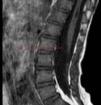

Our patient was a 4-year-old girl with no past medical or family history of interest. She was seen in the dermatology department for evaluation of a lumbosacral patch of hypertrichosis that had been present since birth. Examination revealed a clearly defined triangular area of hypertrichosis situated in the central lumbosacral area (Fig. 1). At the time of consultation there were no signs of spinal cord lesions or alterations of psychomotor development. In view of these findings, lumbosacral magnetic resonance imaging (MRI) was performed to exclude associated spinal dysraphism. This showed an occult meningocele with a defect of closure of the posterior arch, a probable distal dermal sinus tract, and syringomyelic dilatation of the distal vertebral canal (Fig. 2). The patient was diagnosed with occult meningocele with associated lumbosacral hypertrichosis. She remains asymptomatic and is being followed up in neurosurgery.